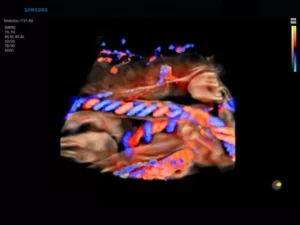

D-режим (допплерография)

Допплерография используется для неинвазивного изучения характеристик движения тканей и жидкостей в организме человека. Наибольшей информативностью этот формат сканирования обладает в диагностике сердечно-сосудистой и акушерско-гинекологической патологии.

Принцип работы режима основан на эффекте Доплера — физическом явлении, представляющем собой изменение частоты отраженного сигнала в зависимости от скорости движения изучаемого объекта. Частота увеличивается с приближением к датчику и снижается при удалении от него. В роли объектов, отражающих эховолны, обычно выступают эритроциты.

Благодаря D-режиму и его разновидностям можно исследовать основные параметры кровотока (направление, скорость, ламинарность), оценить степень васкуляризации патологического очага.

Сканирование, одновременно сочетающее одну из доплеровских методик и визуализацию в В-режиме, называется дуплексным. Оно позволяет получить комплексную информацию об анатомии сосуда (структуре его стенок, диаметре просвета), определить качественные и количественные характеристики гемодинамики. Кровоток, направленный к датчику, картируется оттенками красного цвета, от датчика — в синей цветовой палитре. Турбулентный кровоток отображается в сине-желто-зеленых тонах.

Триплексное сканирование — сочетание В-режима с двумя допплеровскими режимами (к примеру, спектральным и цветовым).

21.jpg

Рис.2. Почка в режимах CFI и PW.

Режим CFI (Color Doppler Imaging, ЦДК, цветовое допплеровское картирование)

Цветовой доплеровский режим позволяет анализировать характеристики кровотока не только в формате графика на осях, но и в виде цветной схемы. На ней красным цветом выделяются потоки крови, идущие по направлению к датчику, а синим — в противоположную от него сторону. Насыщенность оттенка свидетельствует о скорости движения эритроцитов: чем она ниже, тем ярче изображение.

23.jpg

Рис.3. Пуповина плода в режиме ЦДК + LumiFlow (программное обеспечение, устанавливаемое в ультразвуковом аппарате высокого разрешения).

Поскольку исследование в режиме CFI на большой области обладает ограниченной информативностью, спектральная доплерография предоставляет более детальные данные о небольшом участке, оба режима дополняют друг друга и в практической работе применяются совместно.